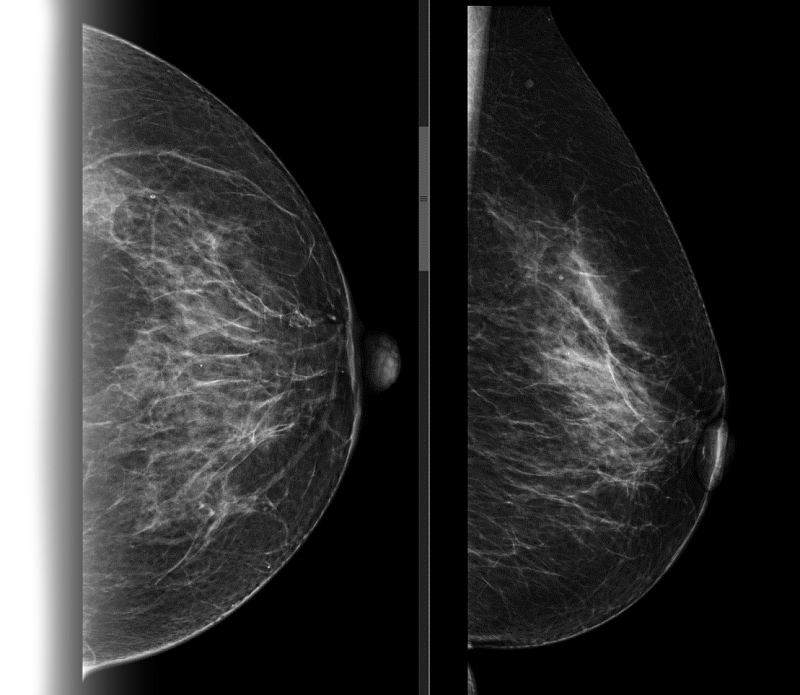

Исследование проводится стоя, предварительно сняв верхнюю и нижнюю одежду области исследования, а также все украшения в области зоны интереса. Для получения четких и подробных снимков, молочную железу располагают между двух пластин маммографа, которые слегка сдавливая, фиксируют ее в неподвижном положении, добиваясь равномерного распределения тканей. Затем специалист делает снимок молочной железы в боковой и прямой проекции. Исследуются поочередно обе груди.